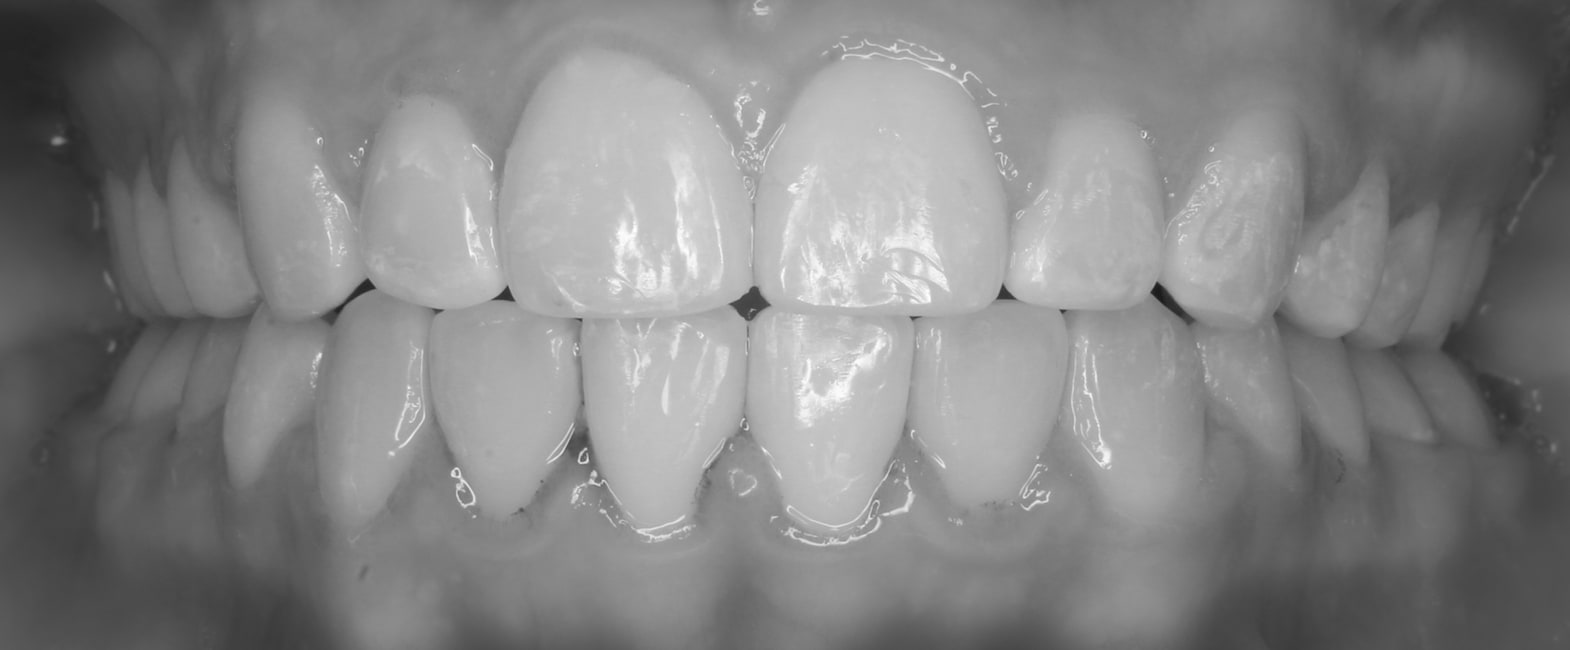

After

Before